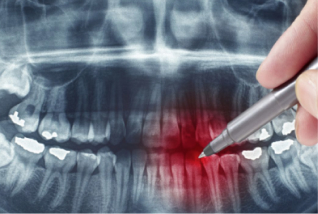

Різновиди щілин між зубами

Медики називають такі прояви діастемами та тремами. Діастема - щербинка між передніми зубами, а трема - між будь-якими іншими, якщо відстань становить більше 1 мм, то необхідно звернутися до лікаря. Більшу увагу приділяють саме діастемі, бо вона одразу кидається у вічі при розмові з людиною.

Причини виникнення щілин між зубами

Стоматологи підкреслюють, що зуби мають торкатися одне одного, щоб утримувати потрібний контакт. Тільки так вони правильно розподіляють навантаження, зменшують кількість шматочків їжі, котрі застрягають в зубах, зупиняють запалення ясен. Якщо ж відкладати вирішення проблеми на потім, з роками проміжки між зубами збільшуватимуться.

Найчастіше діастеми виникають через: